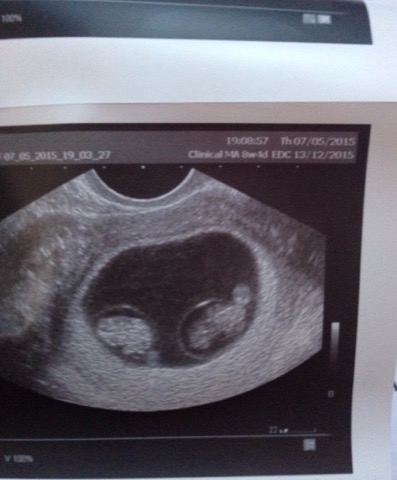

Twins!!!!!!!!!!!!!! May 7, 2015 / Carmen McKnight My baby sister Oana’s going to have twins!!!!!!!!!!! Just found out this myself:)))))) Sora mea cea mica va avea gemeni!!!!!!!!!!!!!!!!! Even little Hadasa is celebrating:) Si Hadasa se bucura de veste:) Share this: Email a link to a friend (Opens in new window) Email TweetLike Loading... Related